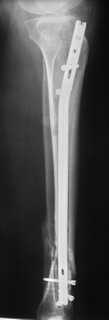

Ранее обсуждаема тема http://weborto.net/forum/1164105478/, http://weborto.net/forum/1192794837/Больная оперирована. Произвели удаление проксимальной части штифта, далее рассверлили канал до 12 мм,Подвели и одели на конец отломка устройство с определенными техническими трудностями( проводник пришлось изогнуть, упиралось при входе в заднюю стенку, что значительно усложнило его последующее вращение, несколько раз удаляли устройство, т.к. полностью утрамбовывалось костной стружкой ) совместили отверстие на втулке и штифте и заблокировали отломком винта ( винт заранее надпилили по диаметру втулки и обломали после введения). Отломок удалился без проблем.Заштифтовали 11 мм реконструктивным штифтом, увы, устранить деформацию полность даже поллер винтами нам не удалось. Интраоперационно на экране ЭОпа оан выглядела не так критически, как на контрольных снимках после операции. Задним умом надо было отложить штифтование после репозиции в аппарате (прав был А.Н.Челноков!), слишком были заняты идеей удаления отломка штифта не оценив проблему устранения деформации. В п/операционном периоде разрешили дозированную нагрузку на конечность.С надеждой на критику и обсуждениеС уважением к сообществу В. Машталов

Судя по р/снимкам у Вас всё отлично получилось, то что немножко допустимое смешение осталось это видимо помешало сросшийся малоберцовка.